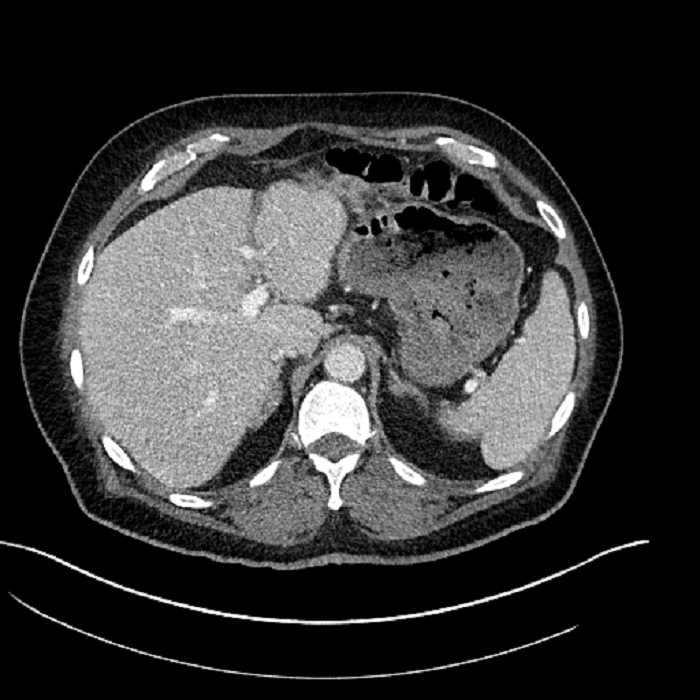

• Large fluid density structure in hepatic segments 7 and 8 measuring 10 x 7 x 7 cm with internal septation and circumferential ill-defined low density compatible with edema

• Peripherally enhancing subcapsular collections along the anterior margin of the left hepatic lobe measuring 3 x 1 cm and 2 x 1 cm

• Hepatic abscess

Acute sigmoid diverticulitis complicated by a small contained perforation and a large abscess in the right hepatic lobe. Additional small subcapsular abscesses along the anterior margin of the left hepatic lobe.

• The classic CT imaging appearance is a double target sign with internal low density surrounded by an internal enhancing rim (capsule) and a low density external rim (edema)

• Abscesses may be unilocular or multilocular

• Gas is present in a minority of cases

Hepatic abscess showing the double target sign with low density internally surrounded by a thin inner enhancing rim (red arrow) and ill-defined outer low density rim (yellow arrow). Blue arrow indicates an internal septation. Red arrows: additional smaller subcapsular abscesses. Red arrow: focal contained perforation associated with diverticulitis.